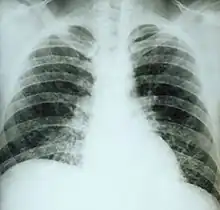

If symptoms of histoplasmosis infection occur, they start within 3 to 17 days after exposure; the typical time is 12–14 days. Most affected individuals have clinically silent manifestations and show no apparent ill effects. The acute phase of histoplasmosis is characterized by nonspecific respiratory symptoms, often cough or flu-like. Chest X-ray findings are normal in 40–70% of cases.[7] Chronic histoplasmosis cases can resemble tuberculosis;[8][9] disseminated histoplasmosis affects multiple organ systems and is fatal unless treated.[10]